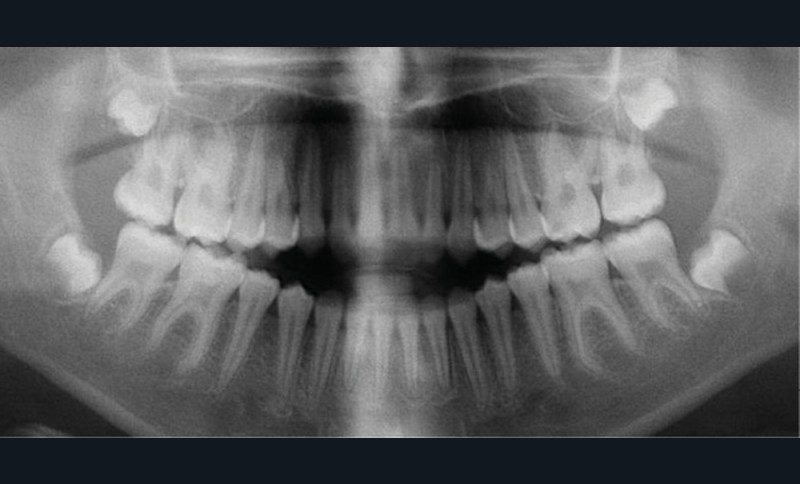

Cette patiente a été suivie dans le cadre d’un traitement interceptif alors qu’elle avait 9 ans. Elle présentait une endognathie maxillaire et une béance antérieure importante liées à des troubles fonctionnels évidents. En effet, l’examen clinique révélait une ventilation buccale exclusive, des ronflements nocturnes et une déglutition atypique. Nous avions noté à l’époque un manque de place pour l’évolution des dents définitives et un inversé d’articulé bilatéral. Les parents avaient rencontré un médecin ORL, mais avaient refusé une intervention visant à enlever les amygdales. Les deux canines maxillaires étaient incluses (fig. 1 à 6).

Quelques années plus tard, au moment de démarrer sa prise en charge orthodontique, la patiente présentait à nouveau une béance antérieure, un décalage des milieux incisifs de 2 mm et le problème transversal avait récidivé. Lors de l’examen clinique, elle présentait un inversé d’occlusion bilatéral postérieur et une ventilation buccale exclusive. À la suite du refus de réaliser l’amygdalectomie de façon précoce, elle ronflait toujours et sa déglutition ne s’était pas modifiée malgré des séances d’orthophonie (fig. 7 à 15).